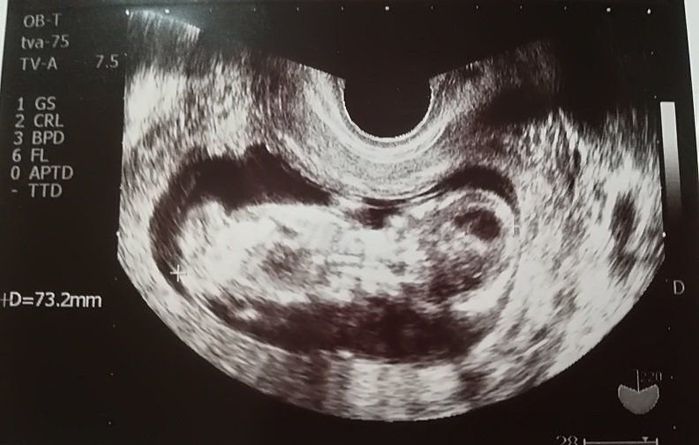

妊娠11週目のエコー写真

頭がはっきり確認できました。そろそろ、つわりがマシになるはずなのに、今度は喉が塞がる感覚で物が飲み込みにくくなるという症状が現れました。耳鼻科では、心身症を疑われて落ち込みました。点滴のおかげか、尿にケトン体が出るまでには至りませんでした。毎日、ネットで他の人のつわりが何週目で終わったのかを調べて励みにしましたが、実際うつ状態だったと思います。